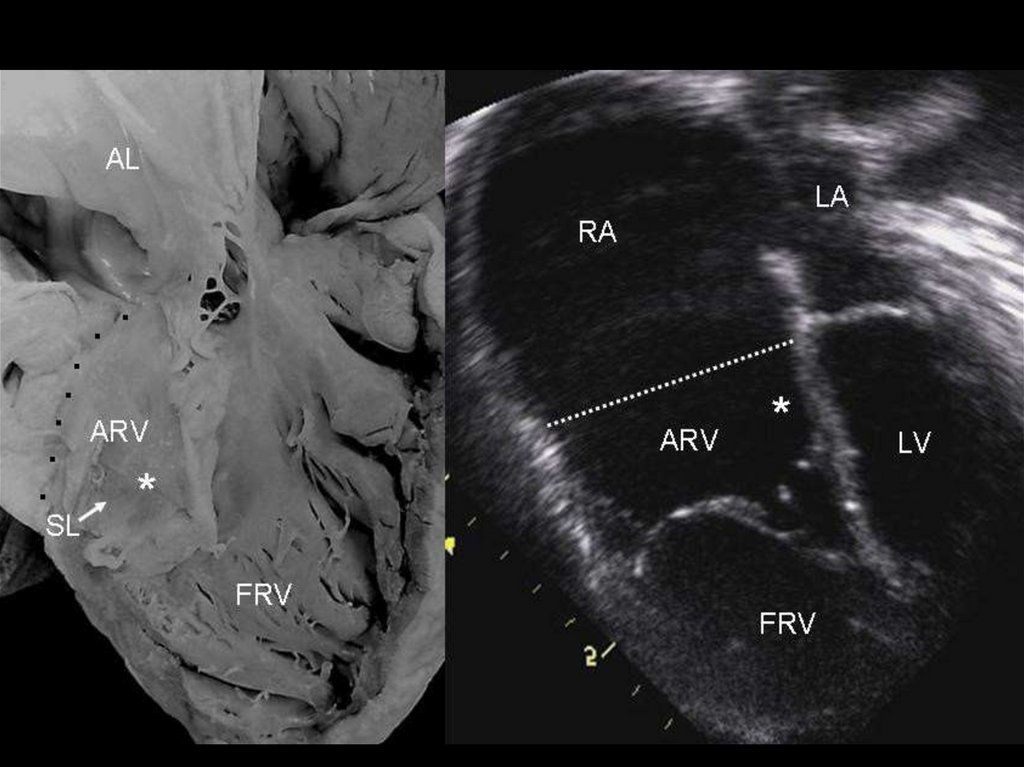

• При этой врождённой аномалии одна или две створки трёхстворчатого клапана расположены не

на должном уровне: они прикрепляются не к фиброзному кольцу между правым предсердием и

правым желудочком, а несколько ниже его; сухожильные хорды этих створок прикрепляются не к

сосочковым мышцам, а к стенкам правого желудочка. Всегда при аномалии Эбштейна в полость

правого желудочка смещается задняя створка трёхстворчатого клапана, достаточно часто – ещё и

перегородочная створка. К атриовентрикулярному фиброзному кольцу остаётся прикреплённой

только единственная передняя створка трёхстворчатого клапана. Эта патология также

сопровождается расширением фиброзного кольца, что приводит к недостаточности

трёхстворчатого клапана.

ЭхоКГ

Метод четко выявляет аномалию, однако существуют специфические черты, на которые

следует обратить особое внимание:

точная оценка створок трикуспидального клапана, их прикрепления и степени регургитации;

целостность межпредсердной перегородки;

целостность МЖП;

оценка размера ПЖ;

проходимость и размер выходного отдела ПЖ и ветвей ЛА;

проходимость артериального протока;

исключение аномалий левой половины сердца.